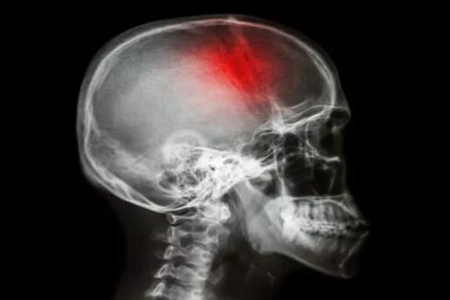

随着生活的水平的提高,中风的几率也随之增加。因为大部分人的饮食都较为追求高营养,多以肉食为主。如此一来人体的脂肪量也在不断增加,血液循环的流量就随之下降,越来越多三高患者出现。一般来说如果是患有高血压的患者,中风的几率会比没有患脑出血几率要高。那么脑出血是怎么引起的呢?

在生活中高血压容易导致脑出血,是众多疾病出现的罪魁祸首,很多脑出血患者是因为高血压诱发的。血压过高的人十分容易出现脑部血管爆裂,造成脑出血。因此患有高血压的人需要做好降压工作,积极配合治疗,日常饮食也要严格控制,避免高血压诱发脑出血。

在生活中情绪波动大经常暴怒或者生气的人容易出现脑出血,情绪波动过大是引发脑出血的一大因素,因为暴怒过程中,人的心跳速度会加快,血压也会快速上升。如果没有及时平复心情,控制好情绪,很容易因为暴怒而诱发脑出血。特别是患有高血压的患者,更加容易因为情绪波动而出现脑出血症状。

在生活中因为长期吸烟会摄入大量有害物质,加速动脉硬化,使人体血管变硬,脆性也会增大,容易导致血管破裂而出现脑出血症状。因此日常生活要养成良好的生活习惯,尽量不抽烟,保证身体健康,减少有害物质的摄入。

在生活中饮酒也是诱发脑出血的一大因素,因为长期酗酒会导致酒精的摄入量过高。饮酒之后人的血压会急速升高,凝血机制也会出现异常,导致人的脑部血流量加快,进而诱发脑出血。当然如果不是长期酗酒,而是一次性饮酒过大也容易导致脑出血。